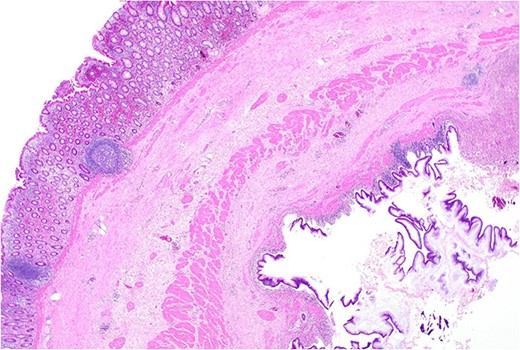

Histopathology macroscopically identified a 42-mm cystic caecal mass adjacent to the ileocaecal valve (Figs 4–5). Microscopic examination revealed a duplication cyst involving the ileal and colonic tissue comprised of a complete duplication of the colonic wall including mucosa, submucosa and muscularis propria, which was shared with the involved colon (Fig. 6). There was no mucosal connection to adjacent normal bowel. There was some ulceration with inflammatory changes in the overlying mucosa suggestive of prior cyst perforation and areas of attenuated villiform mucinous epithelium with features of low grade dysplasia (Figs 7-8). Special stains for organisms (Periodic Acid-Schiff (PAS), Fredericamycin A (FMA), Ziehl-Neelsen (ZN) and modified ZN) were negative. There were no granulomas, heterotopic mucosa or evidence of malignancy. Twenty-nine lymph nodes were identified with no evidence of malignancy.

Remnant of normal colonic epithelium (left) within the duplication cyst that shares common muscularis propria with the terminal ileum (right), low power.